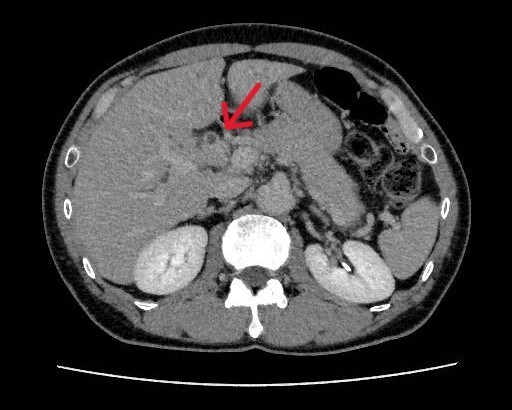

健診にて肝機能異常、皮膚黄染を認め、精査目的で当院消化器内科受診となった。今回実施されたdynamic CTではIgG4関連疾患を疑う所見が認められた。血液検査でもIgG4高値を示しており、IgG4関連硬化性胆管炎と自己免疫性膵炎が疑われ、ステロイドでの加療が開始された。

当該疾患の診断における造影CTの役割